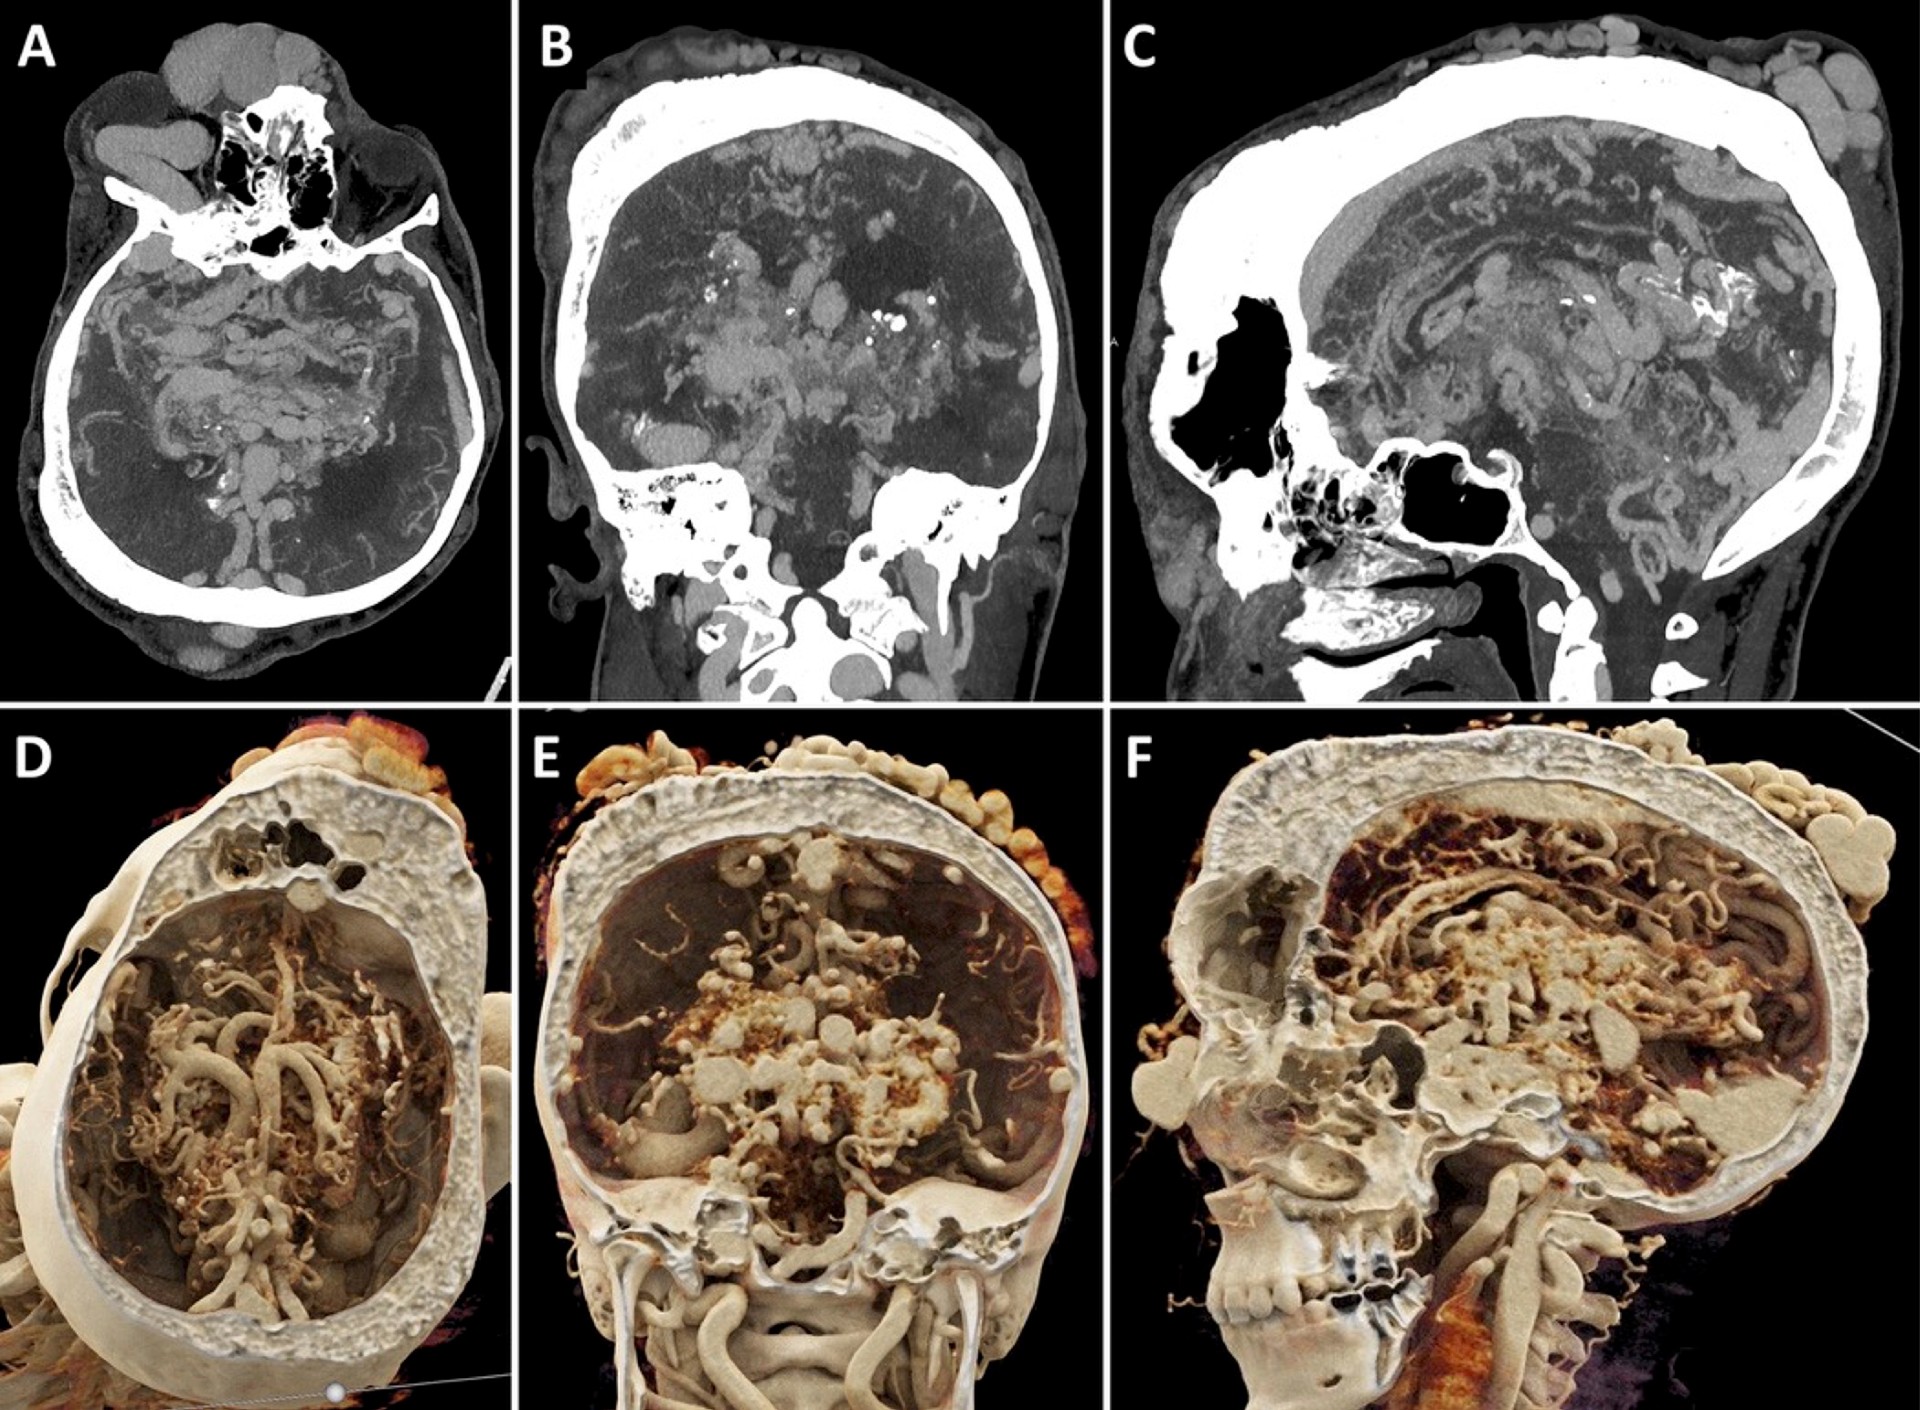

The second runner-up this year is “Calcified Osteosarcoma Lung Metastases” by Paolo Spinnato, MD. The case presents striking CT images of both lungs filled with multiple calcified lung nodules, metastasized from a paraosteal femoral osteosarcoma in a 59-year-old patient. Its significance lies in the vivid reminder that, although calcification in pulmonary nodules is often an indicator of a benign nature of the lesion, the ability of osteosarcoma to produce calcified lung metastases represents an important exception.

Figure 3: Unenhanced chest CT shows osteosarcoma lung metastases. (A) Select axial (1.25-mm thickness) sections displayed in the bone window through the superior (left), mid (center), and inferior (right) chest. (B) Whole-chest maximal intensity projection (left) depicts the overall pulmonary metastatic burden. Three-dimensional volume rendering with chest wall removal (right) shows the intrathoracic lesions in isolation. ©RSNA 2025